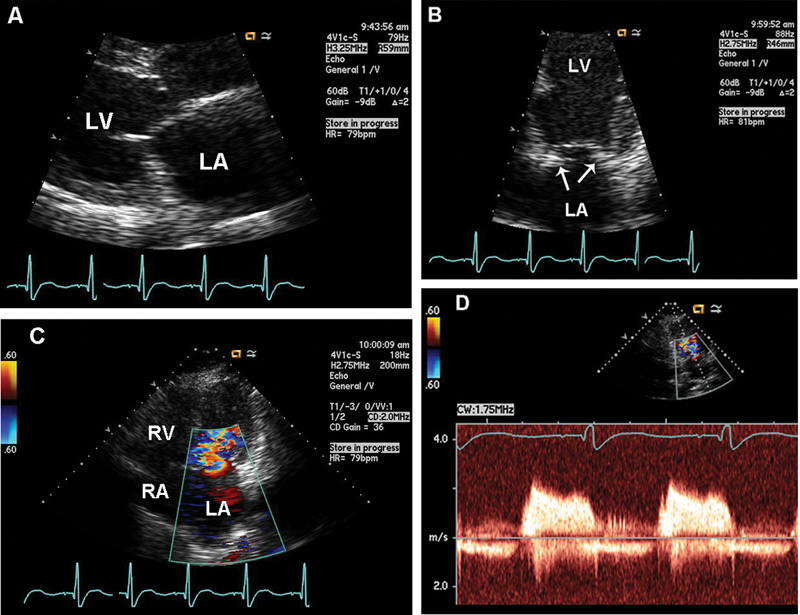

فحوصات تشخيصية لبعض امراض القلب والشرايين التاجية